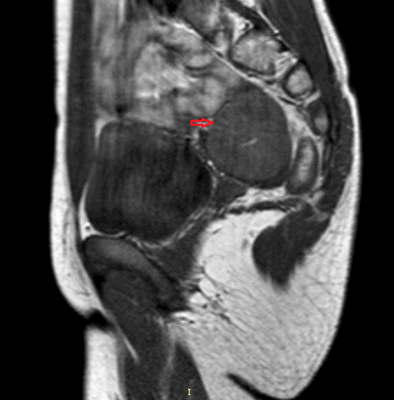

Рисунок 3. - тератома яичника а -УЗИ, б — МРТ.

- КТ (расшифровка: компьютерная томография), МРТ (расшифровка: магнитно-резонансная томография), ПЭТ-КТ (расшифровка: позитронно-эмиссионная томография, совмещенная с КТ). Эти обследования необходимы, чтобы рассмотреть структуры организма послойно и визуализировать опухоль. Они показывают, как сильно распространен патологический опухолевый процесс на находящиеся рядом ткани и органы, есть ли поражение костей. КТ - это самый чувствительный метод для обнаружения метастазов в легких. Проведение МРТ и КТ головного мозга необходимо, чтобы обнаружить и визуализировать герминогенные новообразования эпифиза.

Также выполняют МРТ головного мозга, чтобы выявить наличие метастазов в нем.